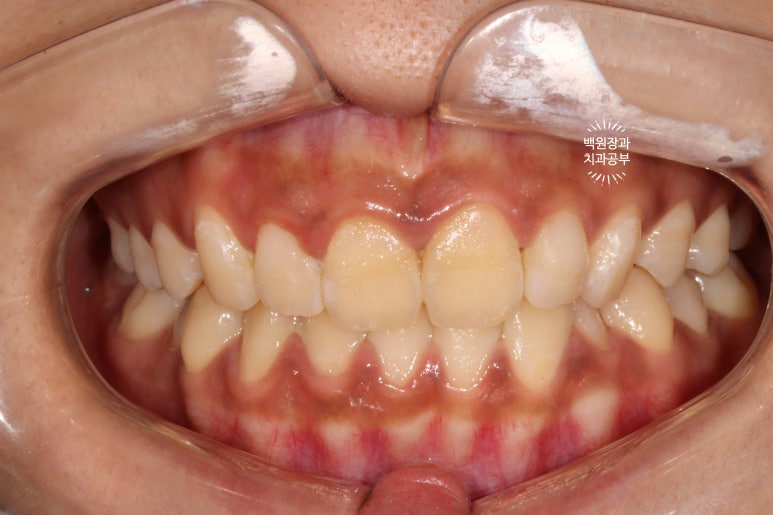

지금 잇몸 상태가 치석제거와 잇몸치료를 모두 완료한 직후입니다.

흡연으로 인한 약간의 잇몸 착색은 있지만, 붉고 부어 있었던 잇몸은 온데간데 없고, 너무나 깨끗한 잇몸상태를 되찾았죠...? 잇몸의 색깔은 선홍색으로 돌아왔고, 날씬하고 얇아진 모습입니다.

이것이 바로 잇몸치료의 위엄입니다!.. 치주과 전문의가 대표원장인 저희 치과에서 가장 많이 행하는 치료이기도 합니다.

앞니 레진은 워낙 변색으로 악명이 높기에.. 약간은 긴장을 하면서 본 환자분의 입 안은....

상당히 잘 유지되고 있다는 것을 볼 수 있었습니다!

저희 치과에서 색조 안정성이라고 부르는데요.. 3년이 지난 시점까지도 이렇게 색상이 잘 유지되고 있는 3M 레진.... 역시 미국제 대기업 제품은 다르다 생각이 들었습니다.

흡연을 여전히 하고계셨고, 3년만에 내원하여 잇몸 속의 치석이 관찰되긴 하였지만 전에 비하면 훨씬 관리가 잘 되고 있었습니다.